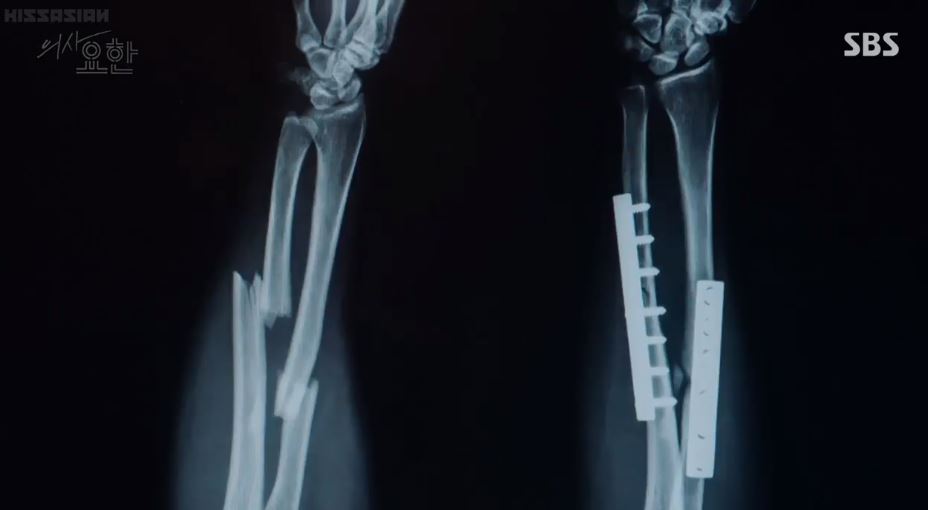

At present Yo Han places the book on the table and connects a hard disk to his computer. He opens a folder titled “NO NAME”. It has numerous folders with dates on them (years). He sees an X-ray of a fractured wrist. There are also many X-rays, which show broken bones and the metal rods and screws holding the bones together.

It looks like Yo Han stitching his wound without anaesthetics at the penitentiary, checking his vitals every day having cold food and tapping his finger till it turned black were subtle hints of his condition – Congenital Insensitivity to Pain with Anhidrosis (inability to feel pain).

I’m guess the X-rays in the hard disk belong to Cha Yo Han.The CIPA patients don’t seem to live over 20 years of age but Yo Han’s father and Yo Han have crossed that age limit. It looks like he is handling it quite well up to now despite the multiple fractures. Yo Han’s past is distressing as he must have had a rough time growing up.